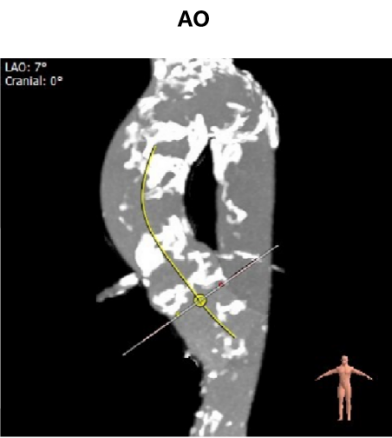

主动脉瓣瓣环周长70.8mm,平均周长径 22.6mm,SOV:31.9mm*28.0mm*29.0mm,瓣叶增厚,瓣上见明显钙化,瓣环水平夹角48°,左冠高度12.2mm,右冠高度15.5mm,HU850钙化积分704mm³。

弓部角度及宽度尚可。